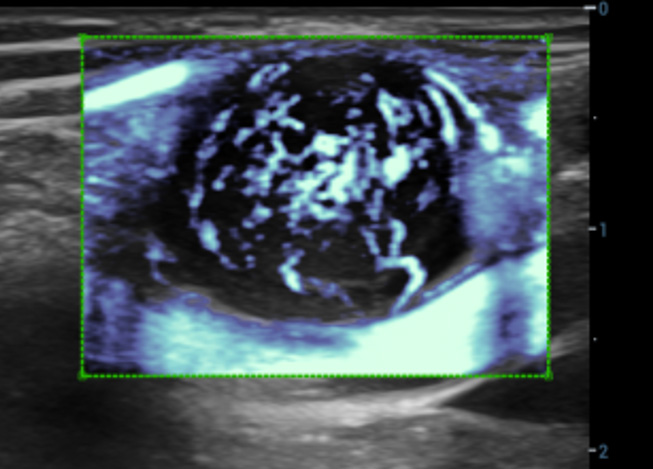

CEUS avan?ado

UWN+ (Ultra-Wideband Non-Linear) CEUS

CEUS ã Tumor maligno de mama

Ao utilizar tanto a segunda harm?nica quanto os sinais fundamentais n?o lineares, o UWN+ permite alta sensibilidade dos sinais das bolhas e maior dura??o de perfus?o com baixo MI, auxiliando nas avalia??es de tumores.

Nova anûÀlise de quantifica??o do CEUS

CEUS QA ã Tumor maligno de mama

A curva tempo-intensidade permite a anûÀlise quantitativa das imagens de CEUS. A nova QA CEUS fornece ferramentas de anûÀlise quantitativa de ponta para ajudar na avalia??o de tumores e na pesquisa clûÙnica.